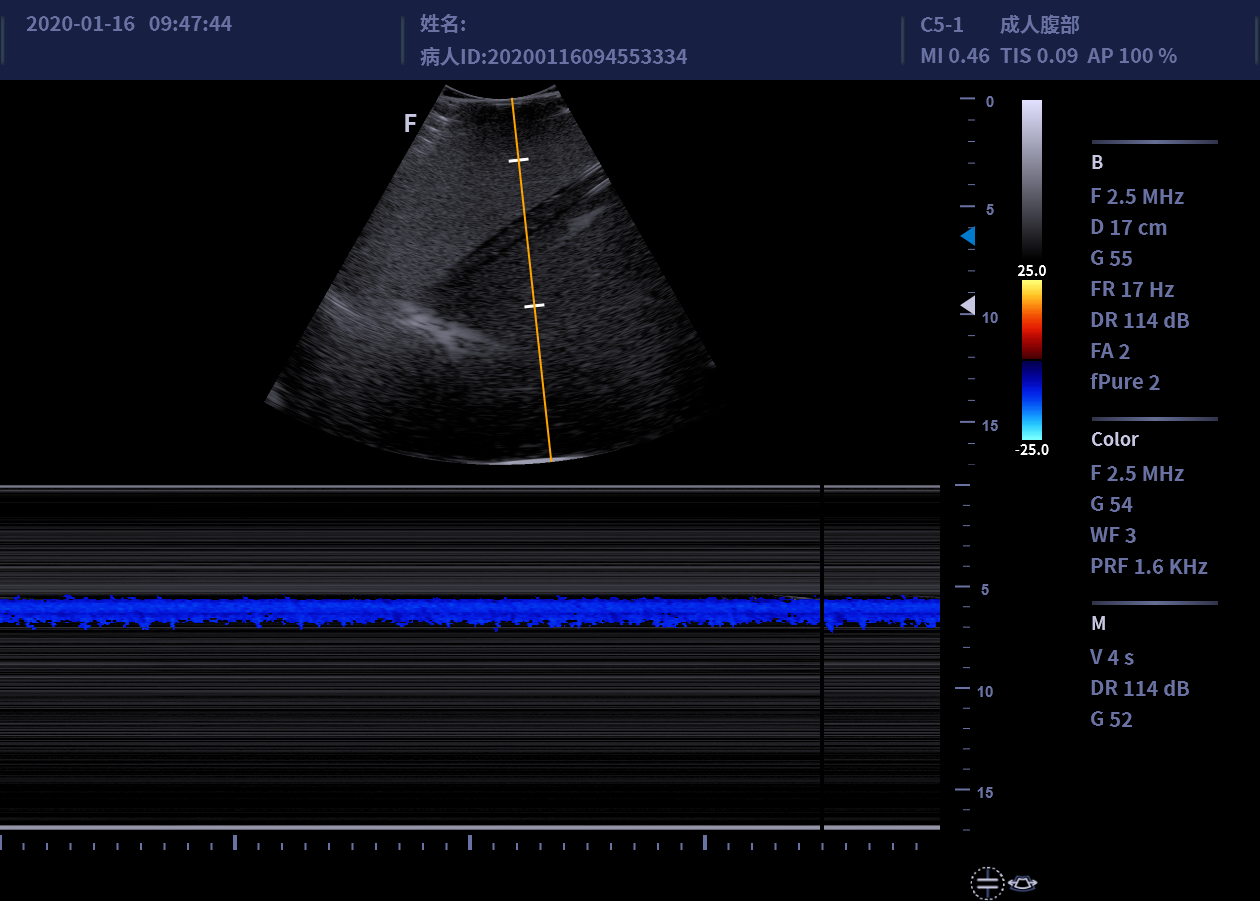

• C5-1/C5-2凸阵探头

适用于腹部、妇产、泌尿等

临床超声检查